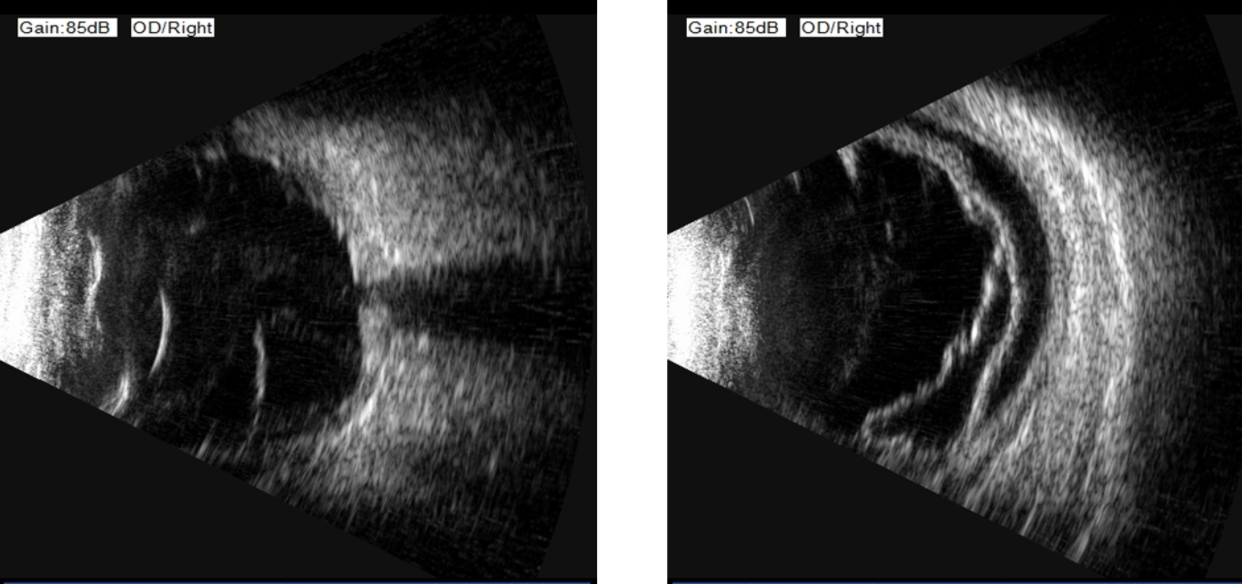

顧名思義,這個病至少包含兩個表現(xiàn):視網(wǎng)膜脫離和脈絡膜脫離。1. 視網(wǎng)膜脫離:視網(wǎng)膜是眼球最內(nèi)層的一層透明薄膜,相當于相機的底片。當它因為視網(wǎng)膜裂孔從依附的壁上“脫下來”時,就形成了孔源性視網(wǎng)膜脫離。患者通常會感到眼前有黑影遮擋,有閃光感、飛蚊癥,脫離累及視網(wǎng)膜最重要的結(jié)構(gòu)——黃斑中心凹時,視力會急劇下降。2. 脈絡膜脫離: 脈絡膜是位于視網(wǎng)膜和眼白(鞏膜)之間的一層富含血管和色素的組織,負責為視網(wǎng)膜提供營養(yǎng)和氧氣。當它因為眼壓過低或炎癥等原因而脫離時,眼底會表現(xiàn)為棕色的“鼓包樣”隆起。當這兩種嚴重的情況同時發(fā)生,就形成了脈絡膜脫離型視網(wǎng)膜脫離。它不僅僅是“底片”脫落,更是“底片”和滋養(yǎng)它的“土壤”一起大面積脫離,對視力構(gòu)成嚴重威脅。

為什么它如此兇險?與單純的孔源性視網(wǎng)膜脫離相比,它具有以下幾個特點,使其更為棘手:1.進展迅猛:病情發(fā)展快,往往在短時間內(nèi)就發(fā)展到視網(wǎng)膜廣泛脫離。2.炎癥反應重:脈絡膜富含血管,它的脫離會引發(fā)劇烈的眼內(nèi)炎癥,導致眼痛、眼紅等癥狀,劇烈的炎癥使治療更加困難。3.低眼壓:低眼壓觸發(fā)了顯著的葡萄膜炎癥和血管滲漏,加重脈絡膜脫離,而脈絡膜脫離又反過來加重低眼壓,形成惡性循環(huán),使病情迅速進展。4.治療更復雜,預后更差: 嚴重的炎癥和低眼壓會給手術(shù)治療帶來巨大挑戰(zhàn),術(shù)后發(fā)生增殖性玻璃體視網(wǎng)膜病變的風險更高,這是導致手術(shù)失敗和復發(fā)的主要原因。